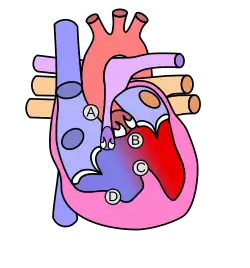

- пороки сердца (врождённые и приобретённые);